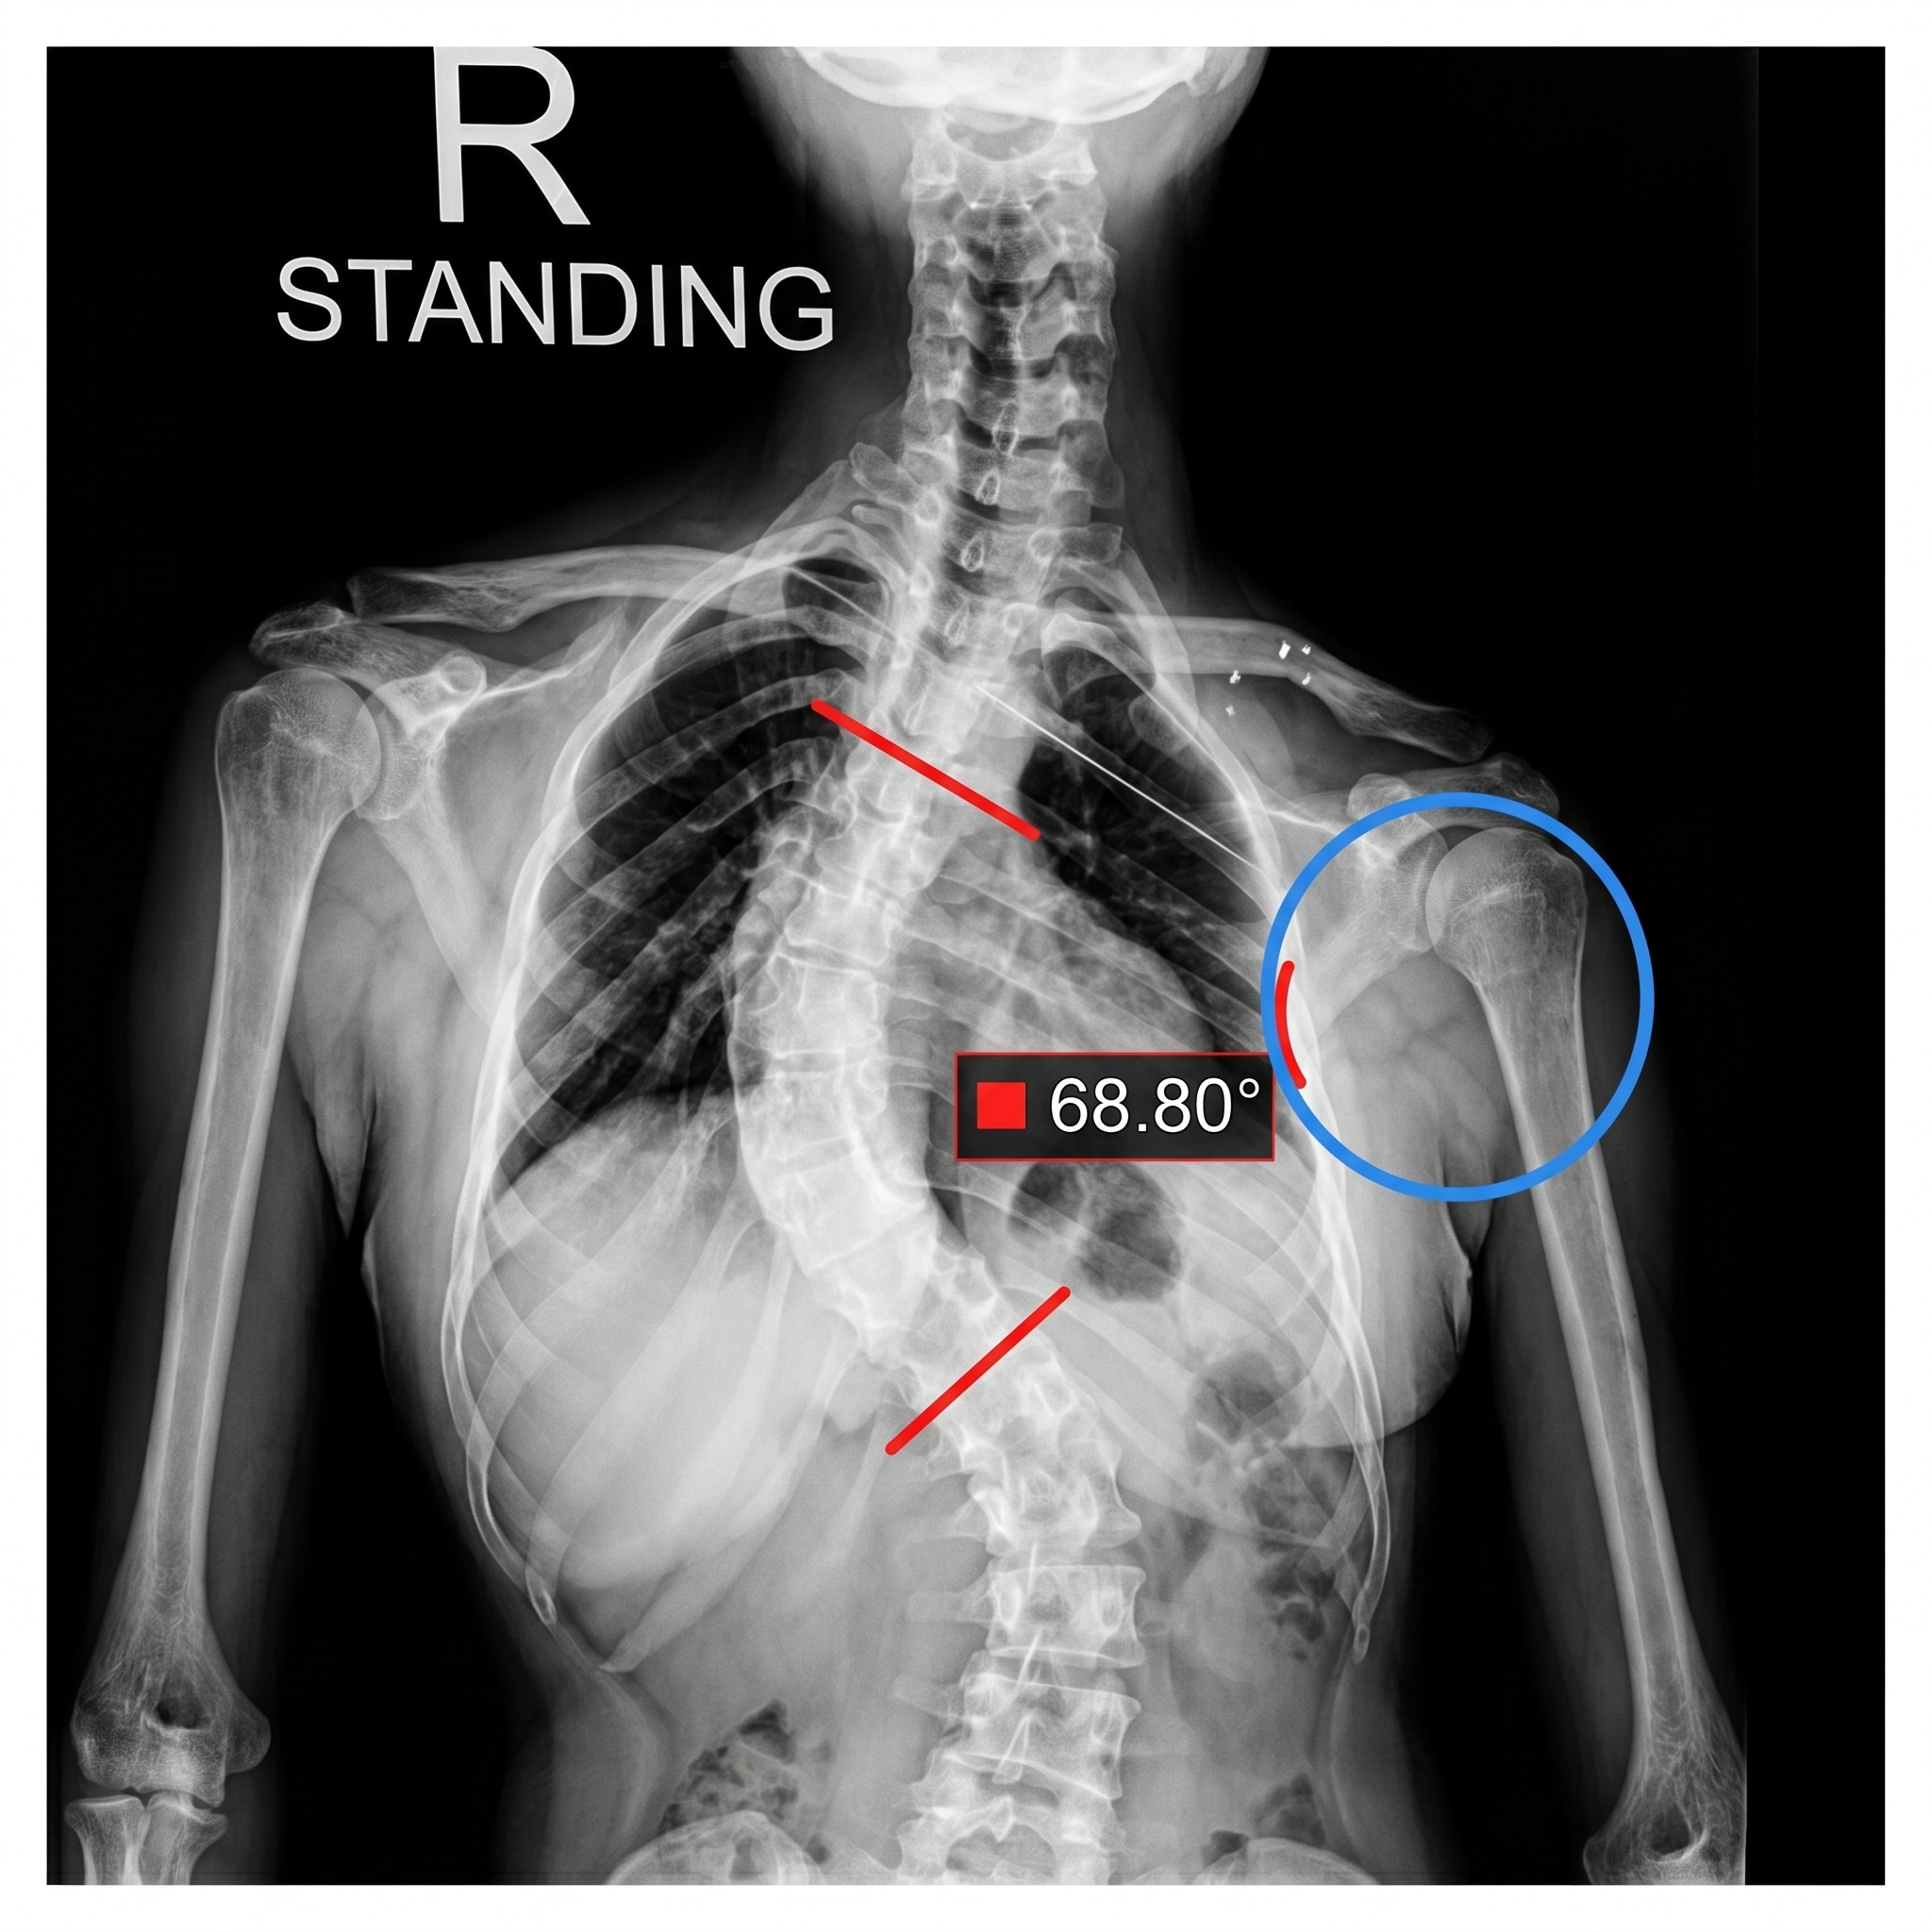

طولت ٥ سم مرة واحدة بعد تعديل تقوس الظهر ..و رغم الام الشد على عضلات الظهر نتيجة فرق الطول الا انها كانت بتتمشى عادي تاني يوم العملية

ركبنا ١٩ مسمار و كسرنا و عدلنا ظهرها المقوس المتيبس بزاوية تعدت ال ٩٠ درجة و رجعناه للشكل الطبيعي.

دا فيديو بيحكي تجربة سيده ٣٧ عام تعاني من #تقوس_مهمل بالعمود الفقري منذ الطفولة ازداد مع الوقت حتى تعدى ال ٩٠ درجة و تم تعديله بنجاح .. في الام اختفت و باقي فقط الام عضلات الظهر اللي اتمطت اكتر من ٥ سم بتخف بالتدريج يوم عن التاني.